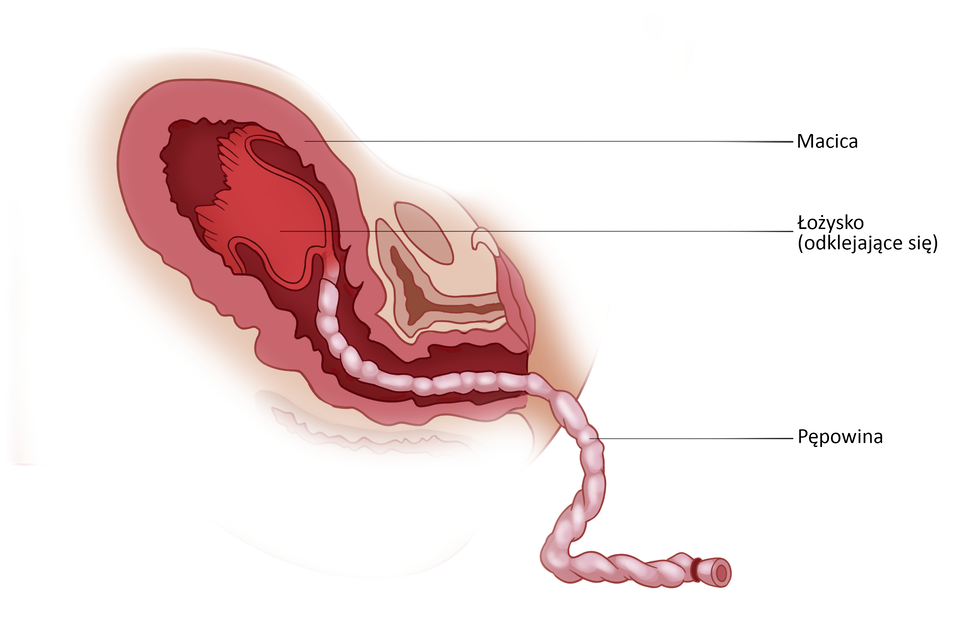

W przebiegu porodu wyróżnia się trzy fazy: rozwierania, wypierania i łożyskową.

Galeria przedstawiająca fazy porodu:

pęknięcie pęcherza płodowego, odklejenie lub nieprawidłowe położenie łożyska